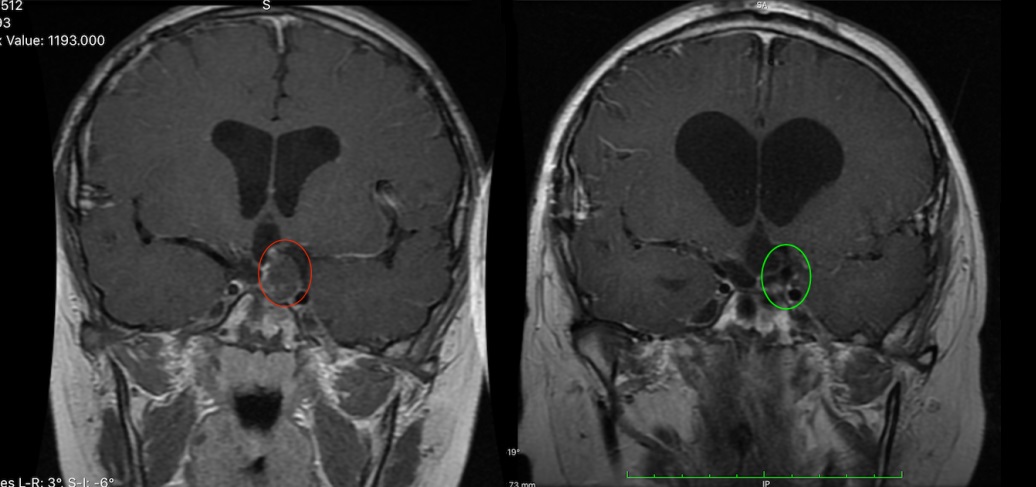

影像檢查顯示,腫瘤從鞍上延伸至第三腦室和橋小腦角區(qū),并已引發(fā)腦積水。隨著腫瘤向“生命禁區(qū)”腦干生長,小安的癥狀也日益加重。為了盡快手術(shù),田先生和家人徹夜失眠,他們不放過任何一絲希望,可結(jié)果卻不盡人意。

顱咽管瘤影像